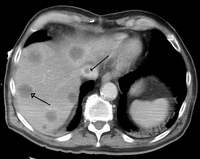

Imaging tests such as transient elastography, ultrasound and magnetic resonance imaging can be used to show the liver tissue and the bile ducts. Liver biopsy can be performed to examine liver tissue to distinguish between various conditions; tests such as elastography may reduce the need for biopsy in some situations.[47]

A previously undiagnosed liver disease may become evident first after autopsy.[citation needed] Following are gross pathology images: